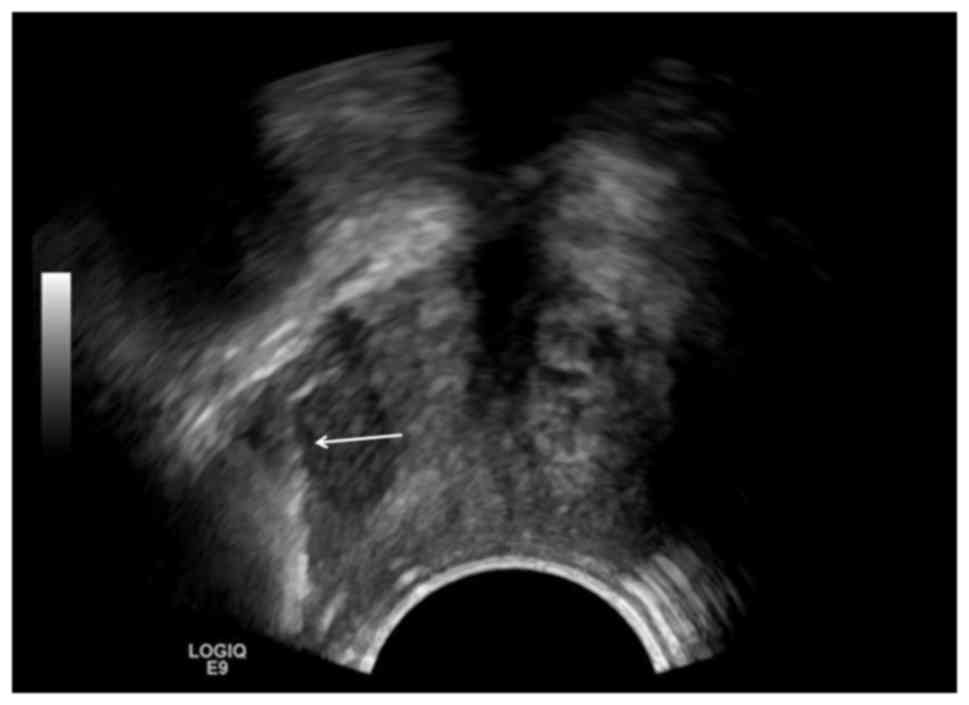

Figure 1.

TVUS of a 67/F patient with endometrial cancer. Biopsy was taken at the vaginal stump, with a mass of 3.0×1.7 cm, indicated by the white arrows. TVUS, transvaginal ultrasound.